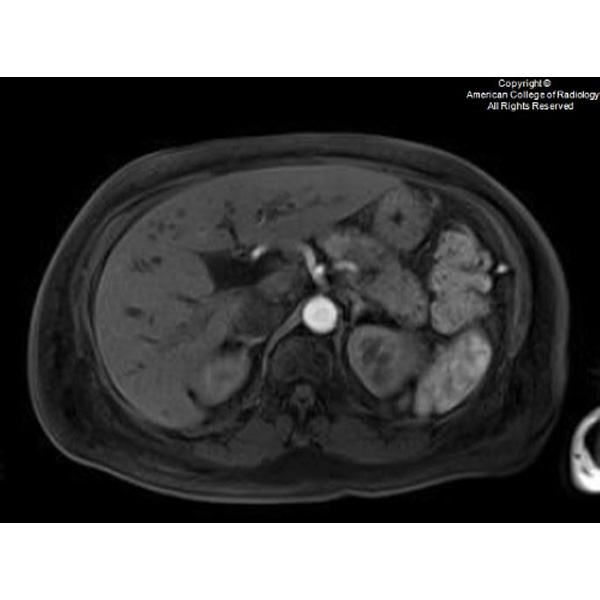

It's time for a new #SARgettable case of the week contributed by Amita Kamath. Comment with your diagnosis down below!